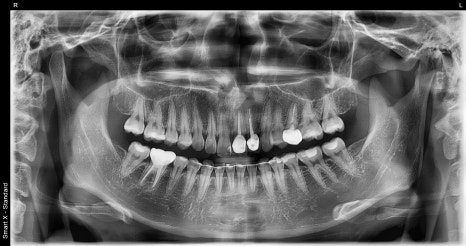

At the first visit, a panoramic image and oral photos were taken

to check the overall dental condition,

and because the color, translucency, and symmetry of the front tooth line

had a major impact on the overall impression,

we determined that a design combining laminate and anterior crowns

would be the most suitable.